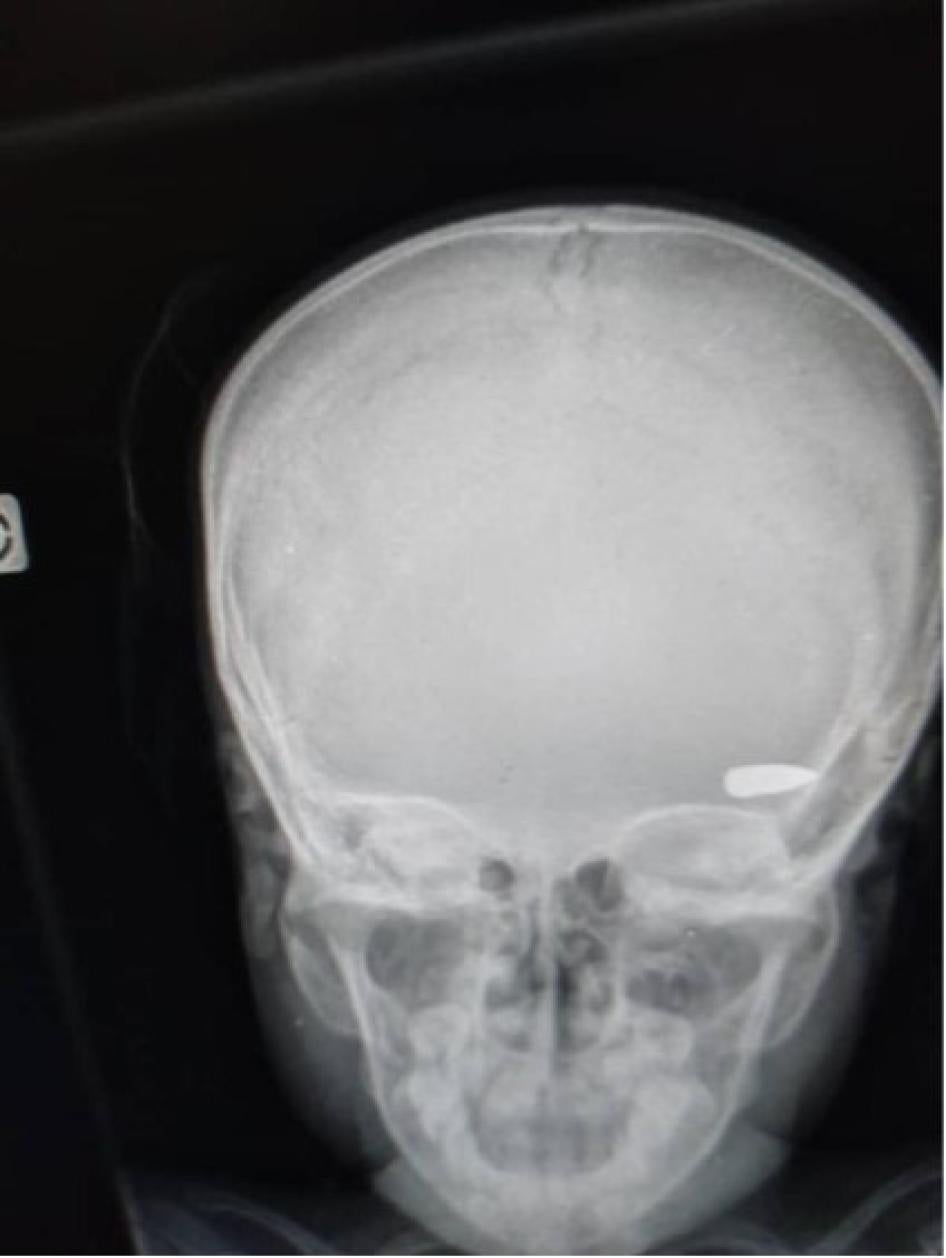

Al menos 45 víctimas murieron por heridas de bala, mientras que otras fueron atacadas con machetes y algunas fueron incineradas vivas dentro de sus casas. La mayoría de las personas que recibieron disparos fueron alcanzadas en la cabeza, el pecho o la espalda, y parecen haber sido el objetivo. Al parecer, dos fueron víctimas de balas perdidas mientras estaban dentro o justo fuera de sus casas, y una víctima recibió un disparo mientras huía de los enfrentamientos entre diferentes grupos criminales. En unos pocos casos, los familiares pudieron recuperar los cuerpos de sus seres queridos para darles sepultura. La mayoría de los cuerpos, sin embargo, fueron quemados en las calles o se los llevaron los grupos criminales[41].

Una radiografía muestra una bala alojada en la cabeza de un niño que fue impactado durante un enfrentamiento entre grupos criminales en el barrio Brooklyn de la comuna de Cité Soleil a principios de abril de 2023. © 2023 Privado

Muchas sobrevivientes de violación dijeron que también fueron golpeadas durante los episodios de violencia sexual, y una dijo que los agresores le penetraron la vagina con un palo. Dieciséis de las víctimas no habían visitado un centro de salud ni habían recibido atención médica antes de que Human Rights Watch se reuniera con ellas y las remitiera a un hospital para recibir tratamiento. Garantizar un acceso rápido a la atención médica para las sobrevivientes de violencia sexual es fundamental porque algunos tratamientos son sensibles al tiempo, como la anticoncepción de emergencia para evitar embarazos no deseados y la profilaxis posterior a la exposición para prevenir la infección por VIH[42]. Algunas sobrevivientes entrevistadas para este informe no tuvieron acceso a estos tratamientos. Muchas describieron el dolor físico continuado, el trauma psicológico y la estigmatización que padecieron tras la agresión.